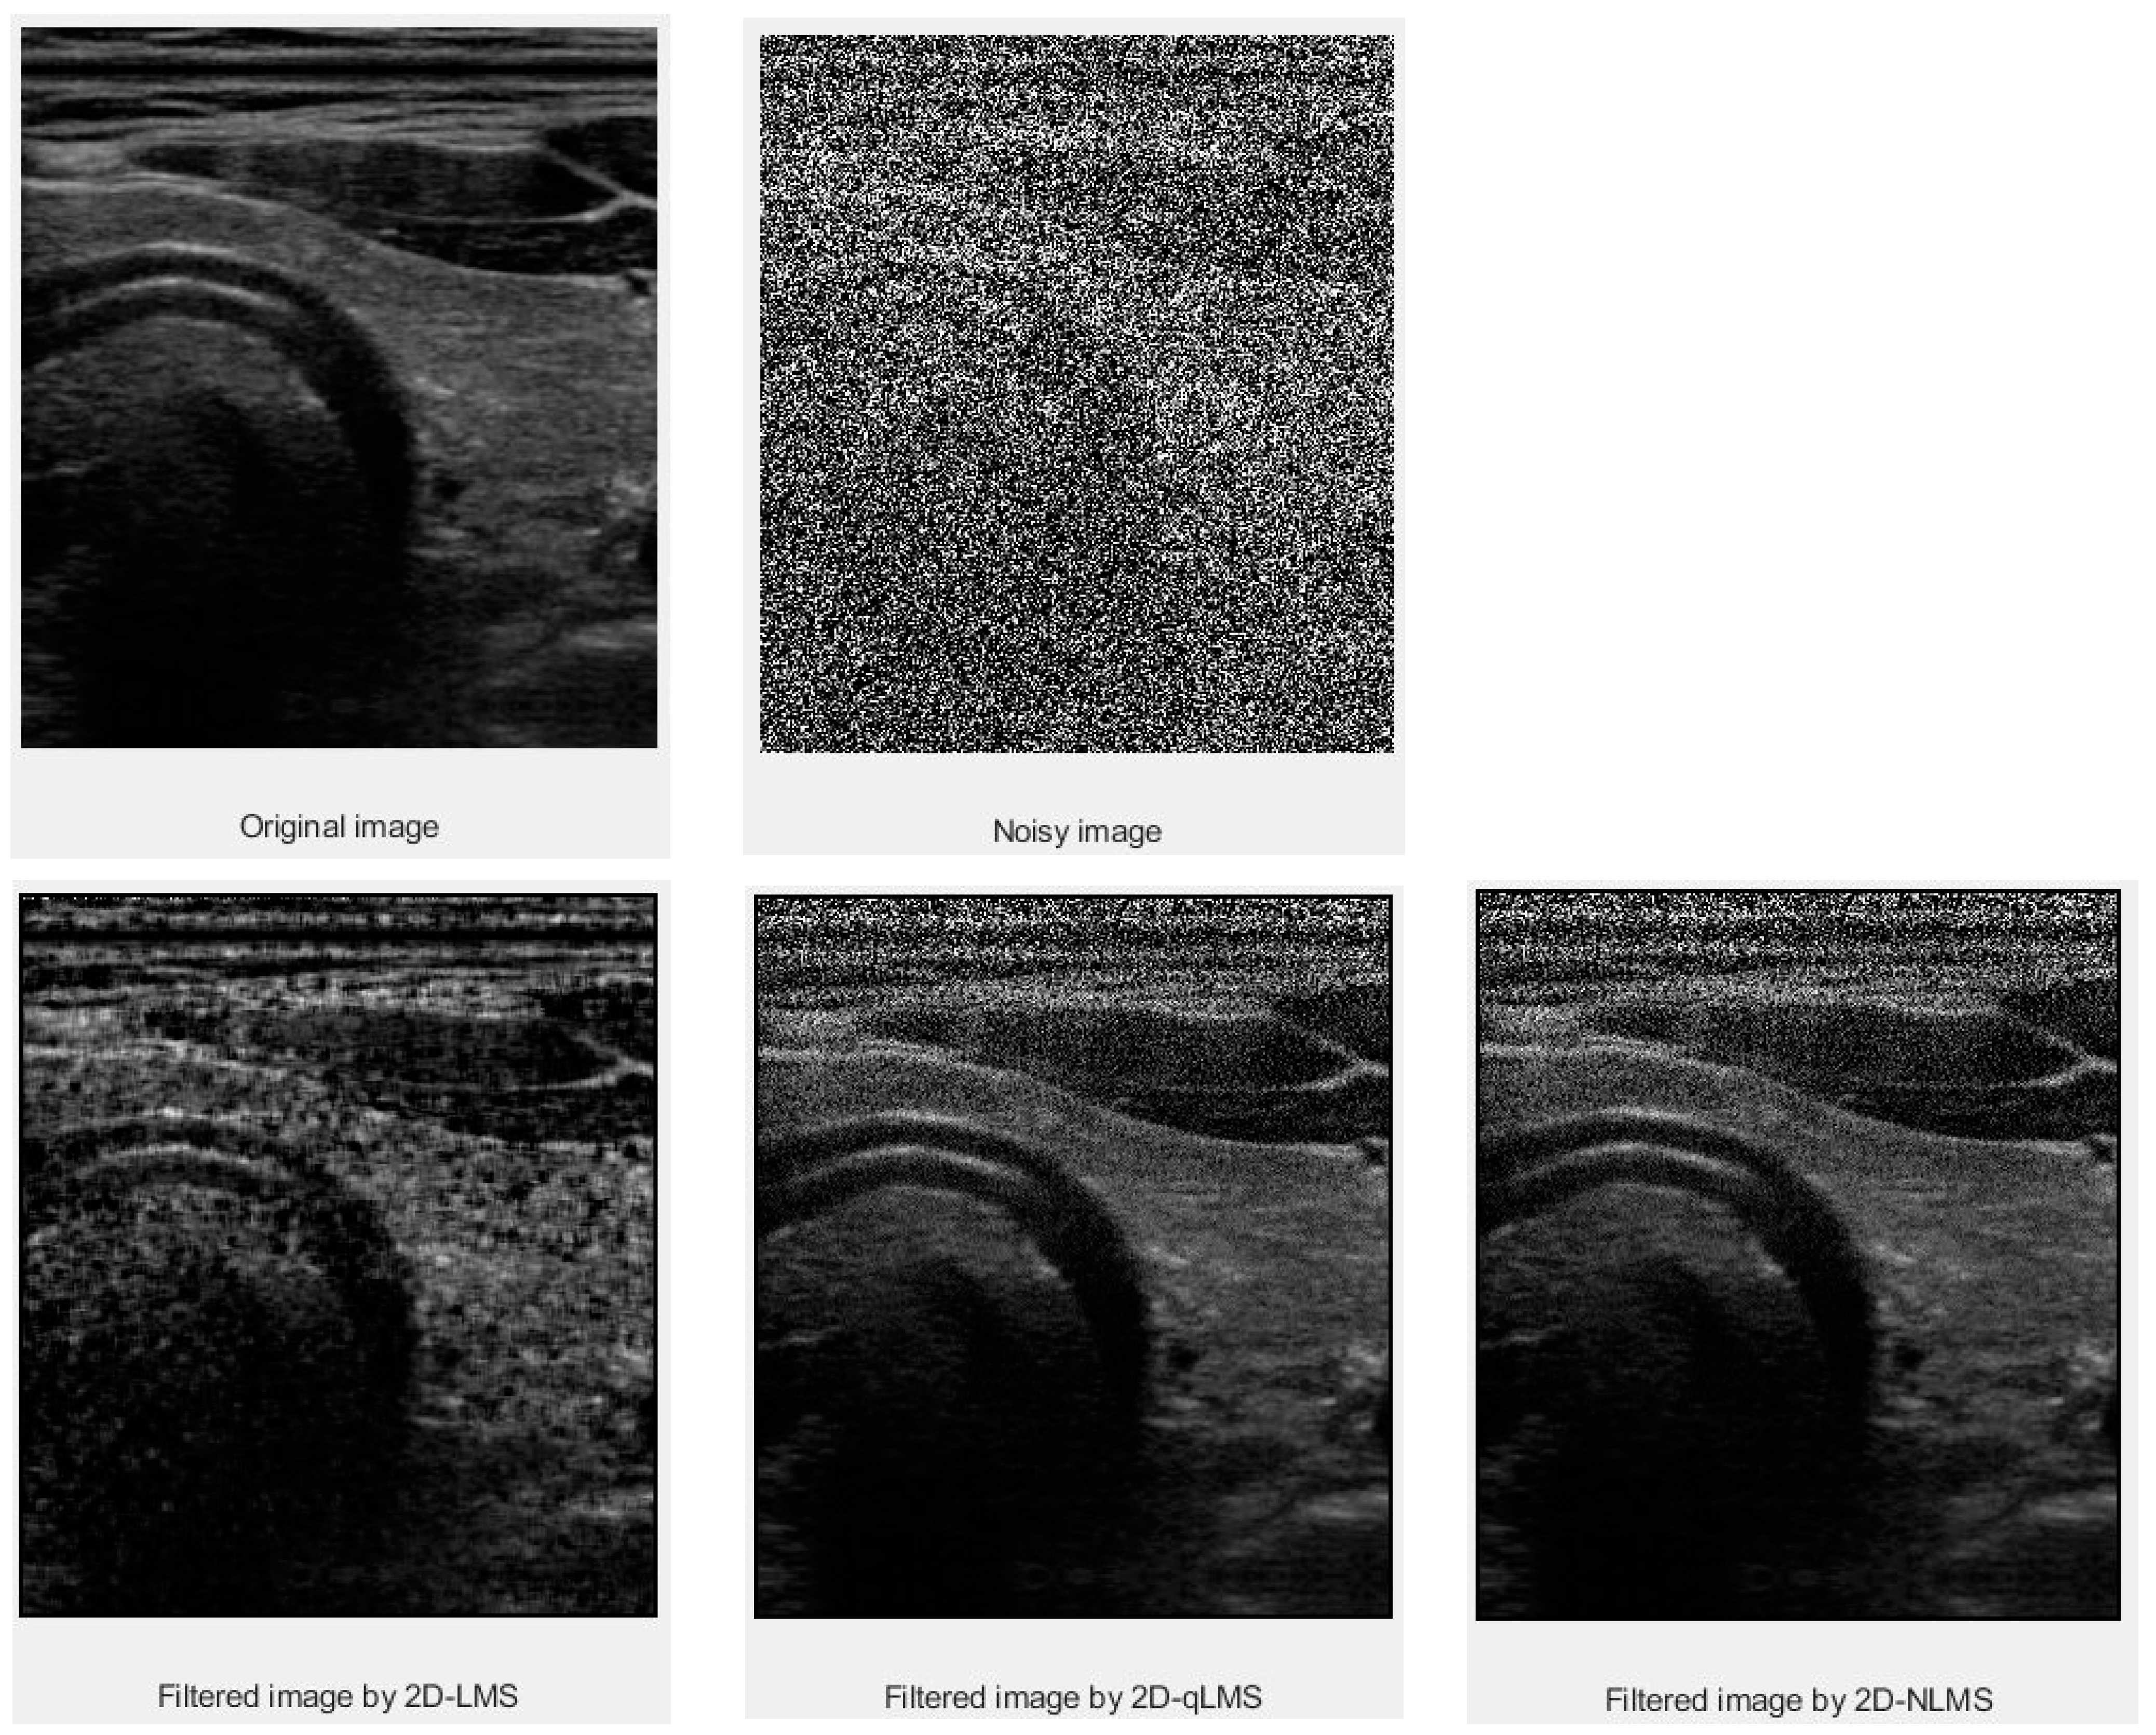

3. Results and Discussion

3.1. PSNR Values

3.2. SSIM Values

| Data | Filter Size | LMS | QLMS | NLMS |

|---|---|---|---|---|

| Thyroid | 5 × 5 | 64.0167 | 70.0593 | 72.8341 |

| Thyroid Cyst | 5 × 5 | 64.0506 | 69.1289 | 72.8708 |

| Mass in Muscle | 5 × 5 | 63.8117 | 69.1211 | 72.2958 |

| Data | Filter Size | LMS | QLMS | NLMS |

|---|---|---|---|---|

| Thyroid | 5 × 5 | 0.9996 | 0.9997 | 0.9998 |

| Thyroid Cyst | 5 × 5 | 0.9993 | 0.9997 | 0.9999 |

| Mass in Muscle | 5 × 5 | 0.9996 | 0.9998 | 0.9999 |